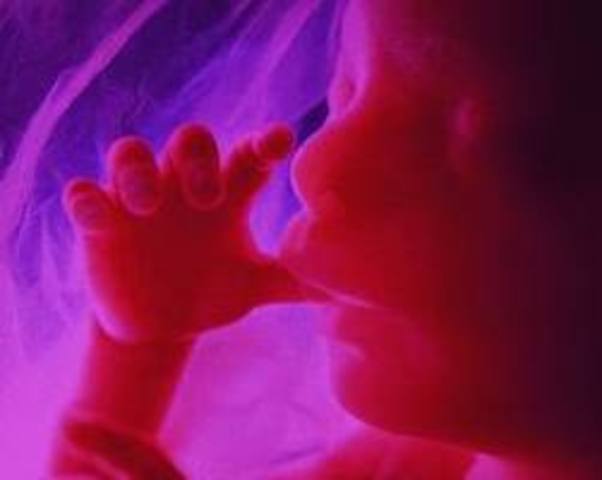

Mom: Fetal movements are strong kicks, thumps, and bumps. The moms has gained about 10-12 pounds.

Baby: about 8-10 inches. Fat dedposits under skin but fetus looks rinkled. Breathing movements are beginning.